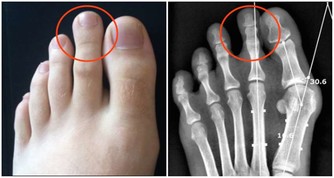

皮膚黏膜損壞後,傷口可能會出現發炎潰爛等症狀,為細菌進入人體提供入口。皮膚被高溫破壞後,肌肉組織大量壞死,為細菌的生存繁殖提供大量養分。尿道,腸道,氣管或血管等受到損傷後,內部壓力增大,細菌可能會進入血液,這也使細菌容易入侵。